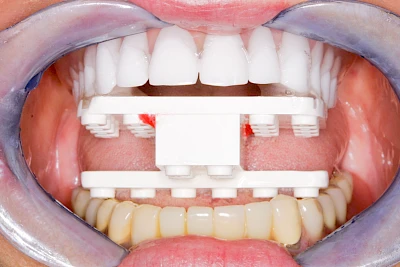

Implantatplanung

Damit Implantate an der richtigen Stelle im Kieferknochen platziert werden könen, gibt es heute vielfältige Möglichkeiten der Planung. In vielen Situationen kann die Erfahrung des Zahnarztes ausreichend sein.

Nicht selten ist jedoch auch eine technisch aufwändigere Vermessung im Vorfeld sinnvoll, z. B.:

- Wenn sich der Kieferknochen abgebaut hat

- Wenn der Nervverlauf im Unterkiefer beachtet werden muss

- Wenn die Ausdehung der Kieferhöhle im Oberkiefer beachtet werden muss

- Wenn wenige Restzähne keine gute Orientierung erlauben

In diesen Fällen kann die Planung mittels verschieden aufwendiger Röntgen-Techniken (Übersichtsaufnahme, DVT) ggf. unter Zuhilfenahme speziell angefertigter Planungsschablonen sinnvoll sein.